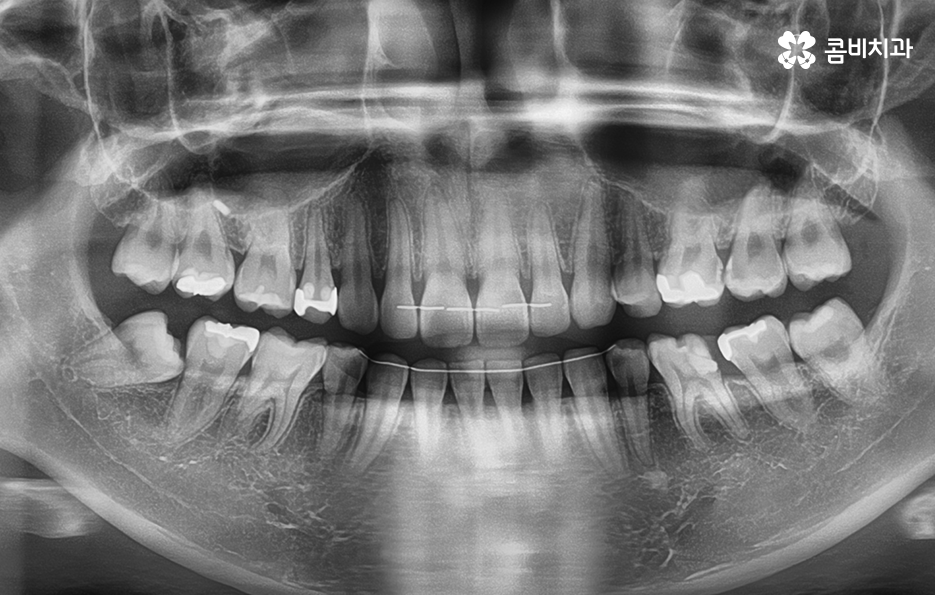

우리가 어릴 때 겪는 충치의 종류는 주로 치아의 씹는면에서 시작된 충치로 씹는면의 충치는 눈에도 잘 띄고 치료적인 접근도 비교적 쉬운 편이기 때문에 치아의 손상 정도에 따라서 적절한 보철 치료를 하면 되는 경우가 많지만 치아 사이 충치의 경우에는 충치를 제거하기 위한 접근 자체가 쉽지 않기도 하고 충치의 발생 위치에 따라서도 치료가 간단하지 않은 경우가 많다는 점에서 예방의 중요성이 유독 큰 충치의 종류라고 할 수 있어요

우리가 어릴 때 주로 발생되는 충치의 유형은 치아의 씹는면에서 주로 발생했다면 나이가 들수록 보철물 내부의 2차 충치나 치아 사이 충치 처럼 눈에 잘 띄지 않고 칫솔질이 잘 닿지 않는 부위에서 주로 충치가 발생되기 때문에 한번 충치가 발생되면 큰 고생을 하게 되는 경우가 많을 거예요

치아와 치아 사이가 맞닿는 부분은 평소 치실이나 치간칫솔을 사용하지 않는다면 칫솔질 만으로는 잘 닦이기 않기 때문에 충치가 자주 발생되는 부위는 아니지만 한번 발생되면 치아 양쪽으로 발생하기도 쉽고 치아 뿌리 쪽이나 신경 쪽에 가깝게 발생되는 경우도 많아서 간단히 레진으로 치료가 어려운 경우가 많고 보통 인레이나 크라운 치료로 이어지는 경우가 많이 있어요